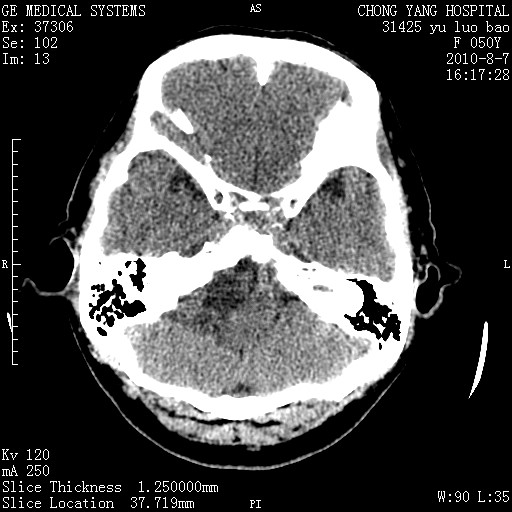

标题: CT28285:听力下降一年,头昏。 [打印本页]

标题: CT28285:听力下降一年,头昏。

右侧桥小脑角区占位--听神经瘤,建议增强或mri检查。

右侧桥小脑角去等密度占位,右侧内听道扩大、骨质吸收,考虑:右侧听神经瘤,建议增强检查。

右侧内听道扩大、骨质吸收,中脑受压左移,考虑:右侧听神经瘤,建议增强检查。支持!

骨窗示右侧内听道扩大,考虑右侧听神经瘤。

右侧桥小脑角区等密度占位,内耳道扩大,听神经瘤